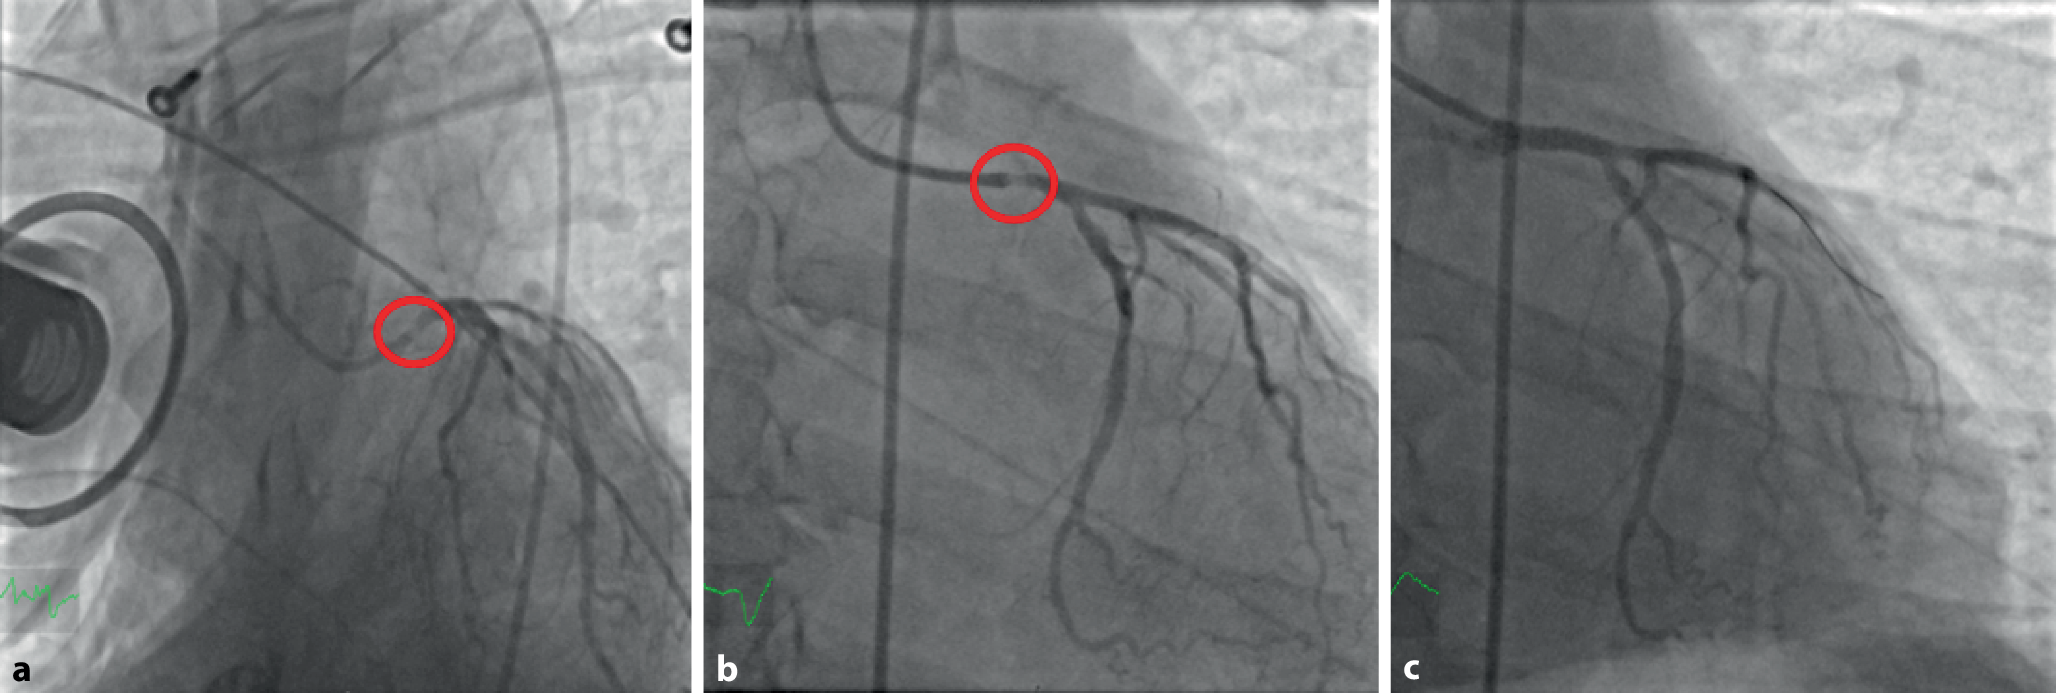

Vierzehn Minuten nach Beginn der Herzdruckmassage erfolgte die Punktion für die Herzkatheteruntersuchung. Dabei zeigte sich eine Plaqueruptur im Hauptstamm (Abb. 2a). Um die Intervention am Hauptstamm ohne die Thoraxkompression des LUCAS-Systems durchführen zu können und um die kardiopulmonale Funktion des Patienten vorübergehend zu überbrücken, wurde im interdisziplinären Konsens die Indikation zur Implantation eines invasiven Kreislaufunterstützungssystems (venoarterielle extrakorporale Membranoxygenierung [VA-ECMO]) gestellt. Siebzehn Minuten nach Beginn der Herzkatheteruntersuchung konnte die ECMO in Betrieb genommen und LUCAS gestoppt werden (Abb. 2b: Koronarangiographie nach ECMO-Anlage). Anschließend erfolgte eine perkutane transluminale Koronarangioplastie (PTCA) mit Stenting des Hauptstamms mit einem „drug-eluting stent“ (Abb. 2c). Danach zeigte sich eine langsame ventrikuläre Tachykardie, die durch zwei Elektrokardioversionsversuche terminierbar war. Die linksventrikuläre Pumpfunktion war echokardiographisch hochgradig eingeschränkt.

Abb. 2

Koronarangiographie a unter laufender LUCAS-Reanimation mit Darstellung einer Plaqueruptur des Hauptstamms (rot markiert), b nach Anlage der VA-ECMO mit Darstellung einer Plaqueruptur des Hauptstamms (rot markiert), c nach Versorgung der Plaqueruptur des Hauptstamms mit einem „drug-eluting stent“